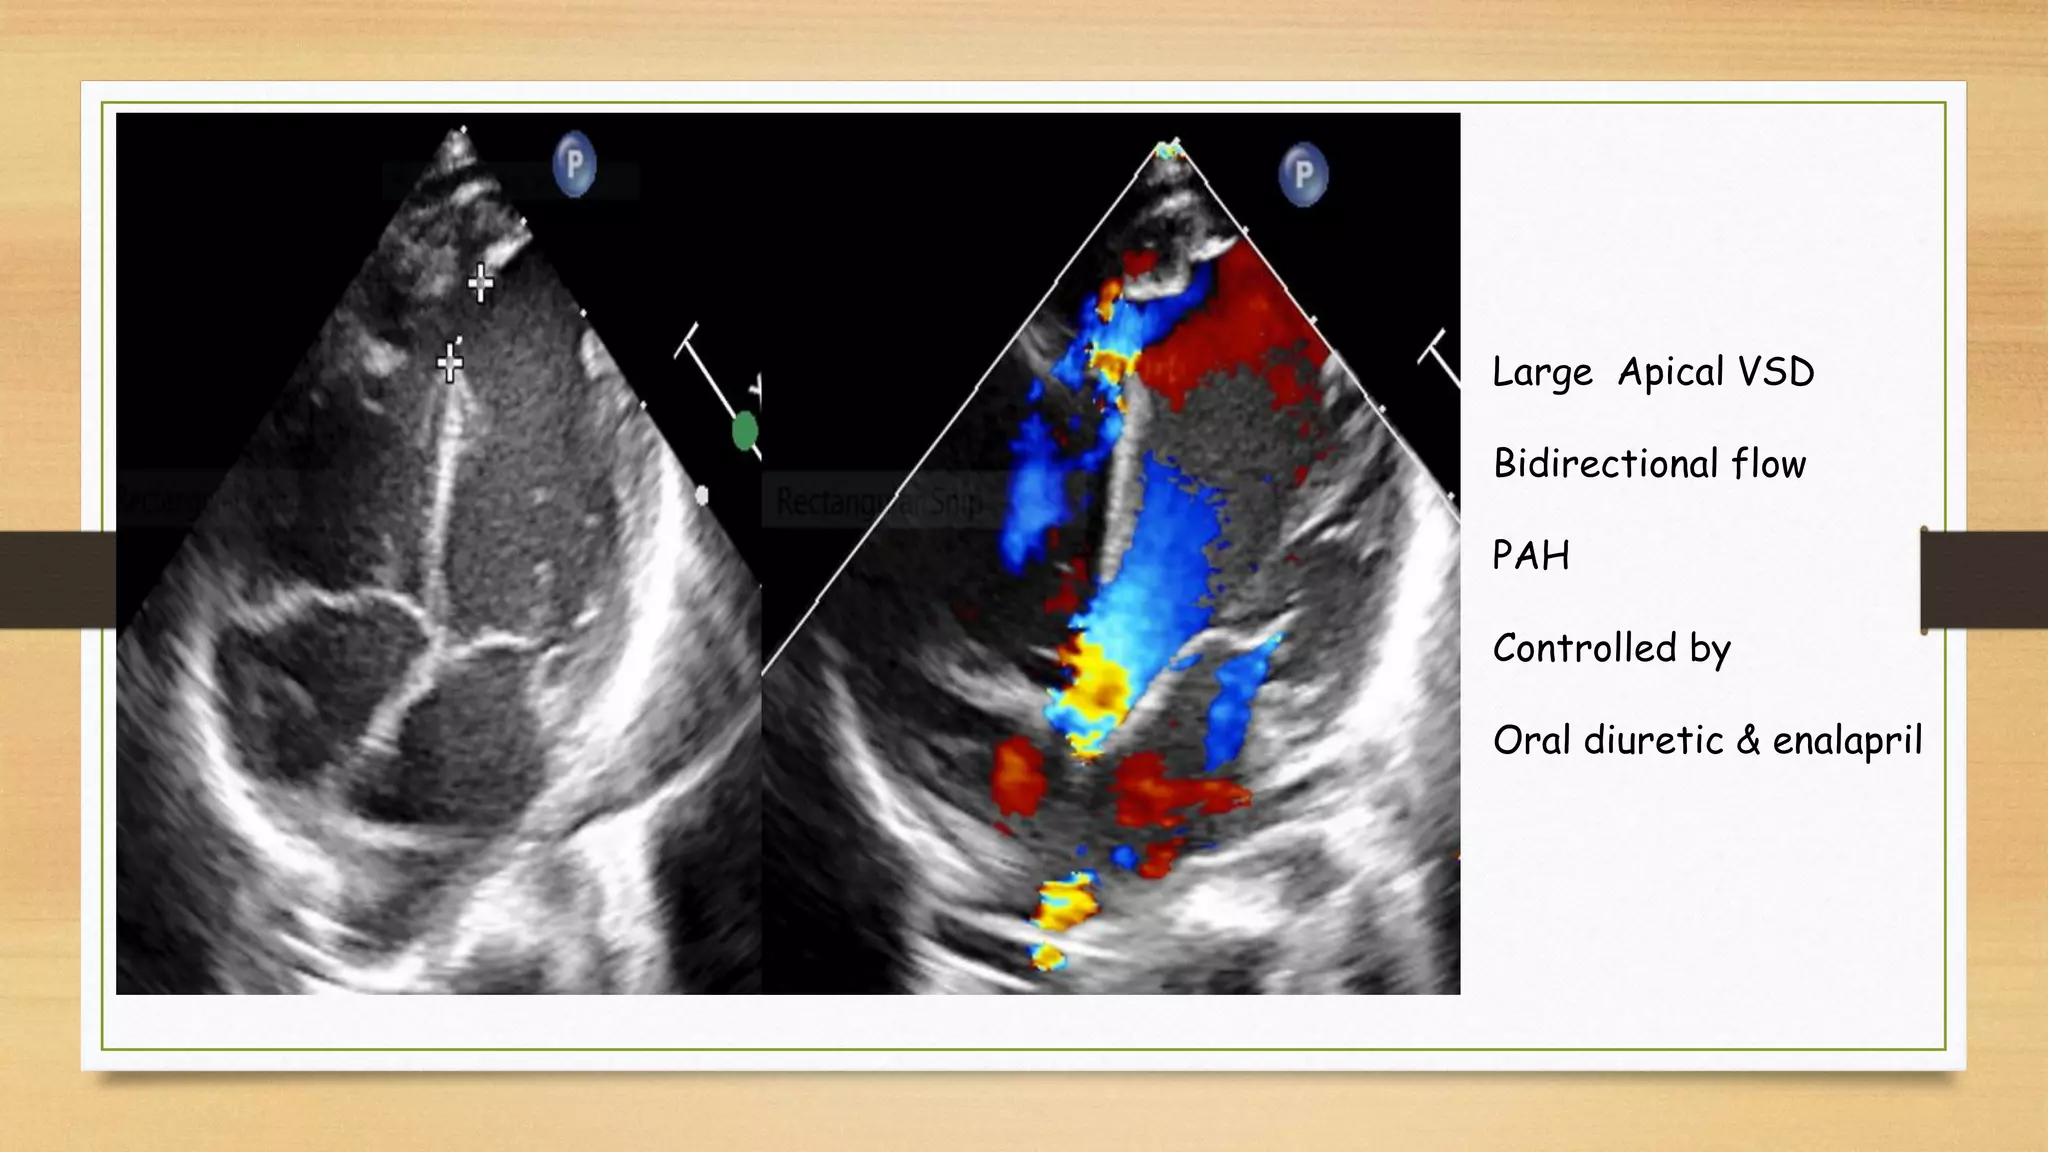

Large Apical VSD

Bidirectional flow

PAH

Controlled by

Oral diuretic & enalapril

Large Apical VSD Bidirectionalflow PAH Controlled by Oral diuretic & enalapril